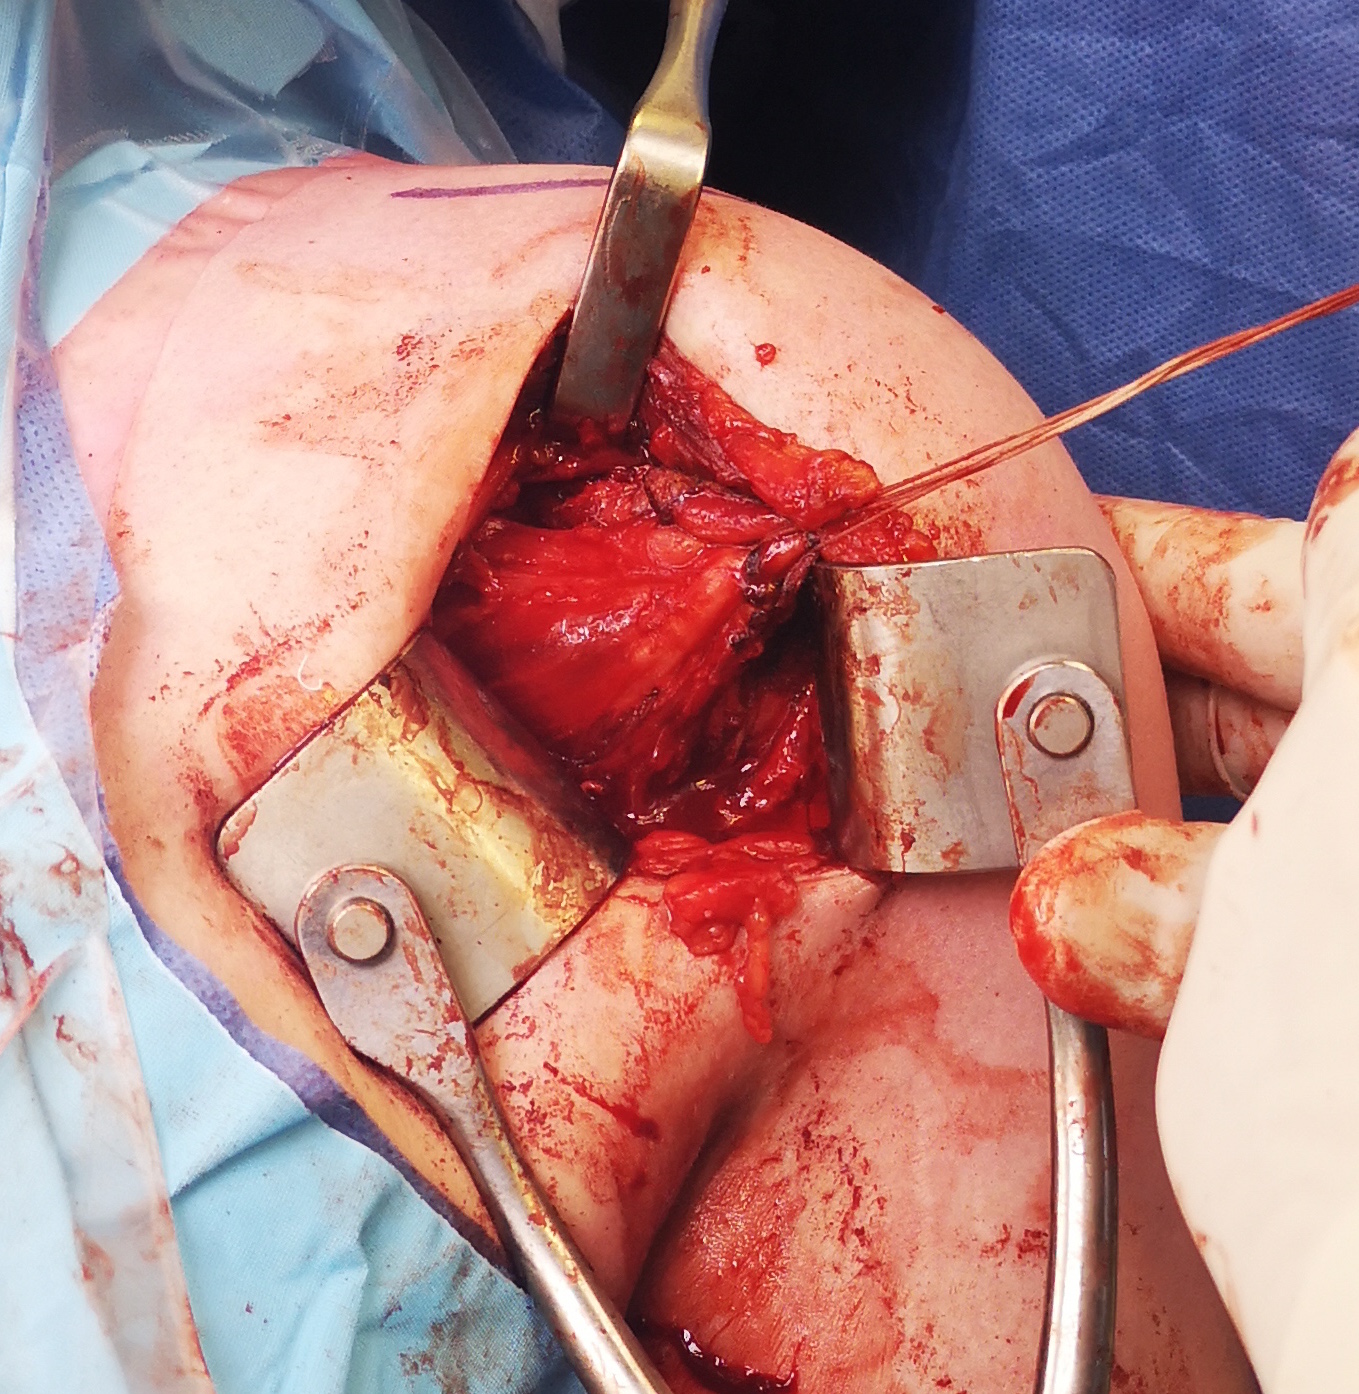

Deltopectoral approach

- split subscapularis

- can perform subscapularis tenotomy and later tighten / Putti Platt

- T shape capsulotomy of capsule

- vertical component on articular margin humeral insertion all the way posterior

- transverse component to midpoint glenoid making superior and inferior flaps

- superior advancement inferior capsular flap

- eliminate inferior pouch and reduce posterior capsular redundancy

- then suture down superior flap